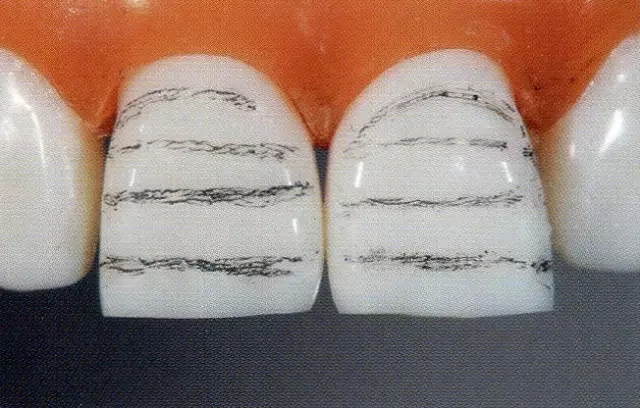

圖1 失敗的牙體預(yù)備。用硅橡膠模型確認(rèn),得出右上1的唇側(cè)打磨量過(guò)多。

另外,貼面也是不是日常臨床中經(jīng)??梢宰龅剑才c全覆蓋冠和嵌體等不同,所以牙體預(yù)備上很多處理都讓人丈二和尚摸不著頭腦。想必這個(gè)很多醫(yī)生都經(jīng)歷過(guò),在修整預(yù)備好的牙體時(shí)會(huì)有制備過(guò)度的問(wèn)題。(圖1)

重要的是要事先腦海里擁有預(yù)備牙體形態(tài)。應(yīng)用硅橡膠印??梢源_認(rèn)牙體預(yù)備的深度,其原則就是打磨就停留在牙釉層。